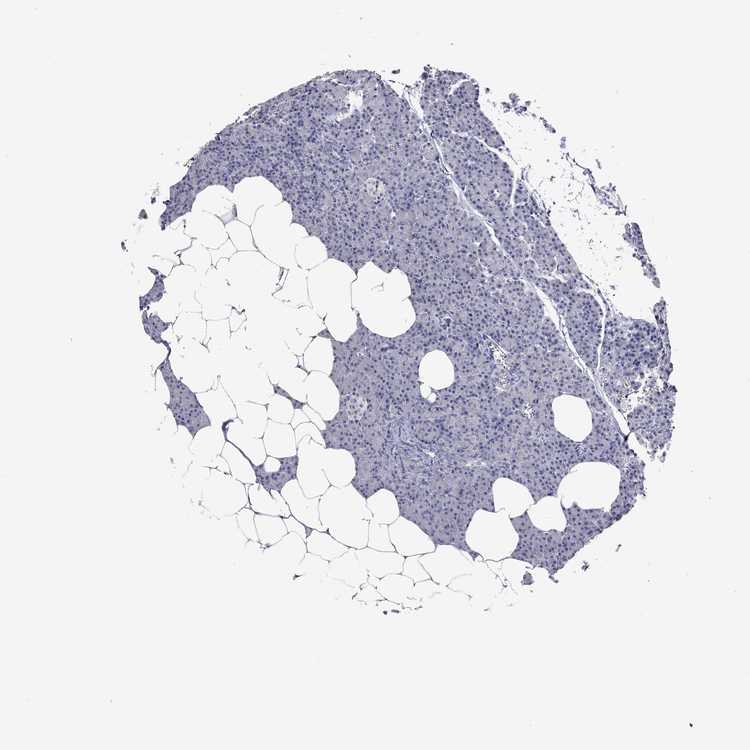

Information about each individual sample is listed below, including gender, age, a tissue section image and estimated fractions of cell types. pTPM (transcripts per million) values give a quantification of the gene abundance which is comparable between different genes and samples.